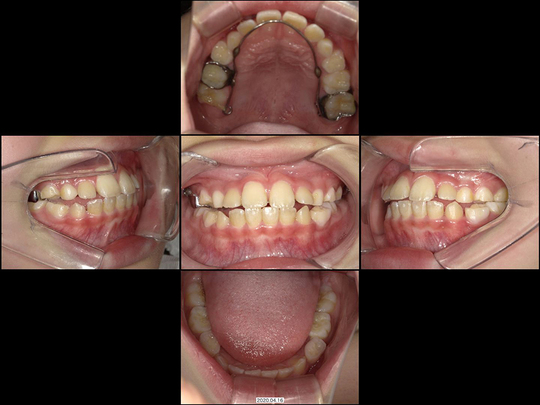

固定式拡大装置 終了

画像をクリックで拡大

治療の説明

将来的にあごの骨を切る外科手術が必要になると診断される状態で困っておられました。

精査の結果、上下の前歯が早期接触したため上下あごの位置がズレたことが発端で、反対咬合になっていることが判明。骨格的な下顎前突(かがくぜんとつ)ではありませんでした。スタート時点では1期治療より前の時期であり、ご本人のキャラクターも考慮してマウスピース型咬合誘導装置を用いることとしました。

上下の前歯の早期干渉による下あごのズレを改善し、固定式拡大装置にて前後的なあごのズレと、小さい上あごの幅を拡げ、乳歯から永久歯への生え変わりをサポートしました。抜歯することなく、またワイヤーの装置を用いることもせずに治療を終えられたケースです。